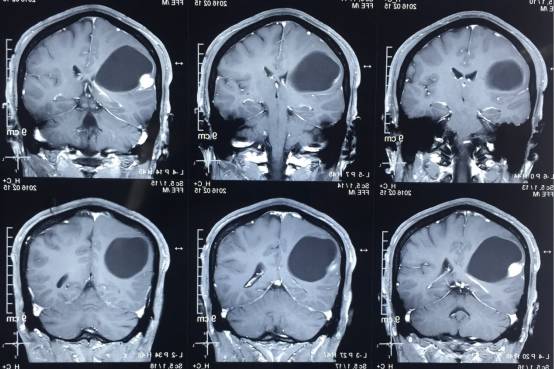

头颅MR示:右颞顶囊性占位伴结节,考虑胶质瘤可能。MRI T1为等信号(图1);T2囊液为高信号(图2);结节为均匀增强(图3);弥散相显示弥散受限(图4)。

图1. MRI T1为等信号。

图2. T2囊液为高信号。

图3. 结节为均匀增强。

图4. 弥散相显示弥散受限。